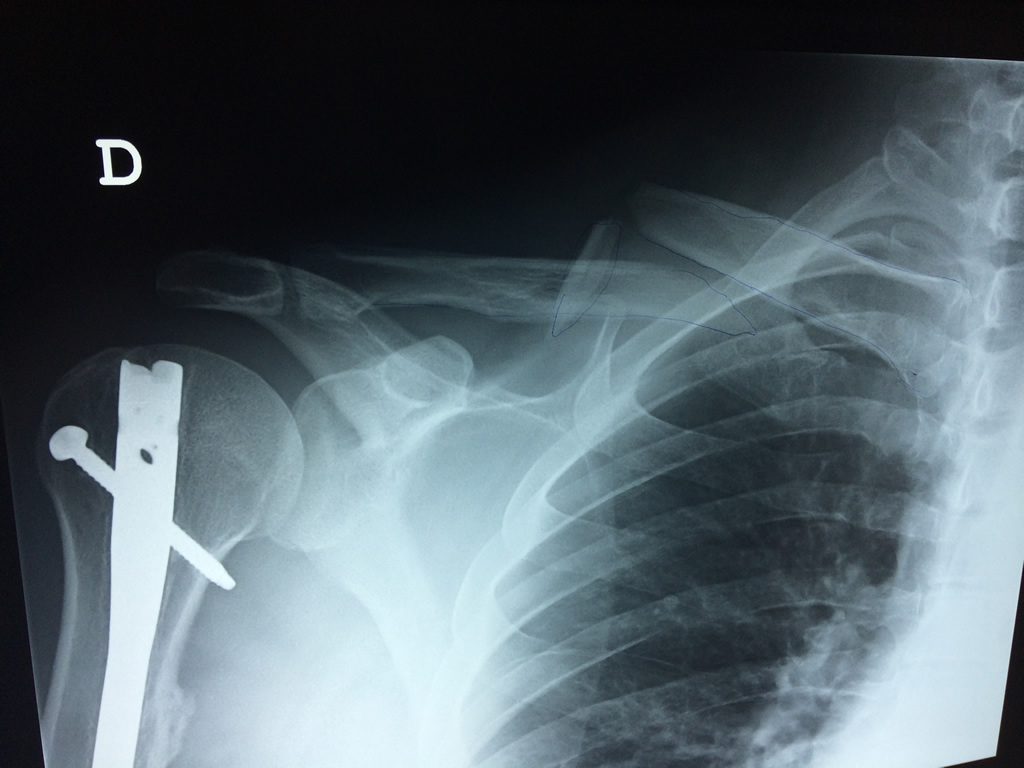

Cirugías de Húmero - Clavícula